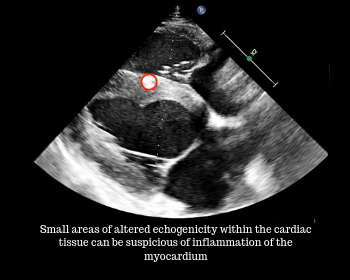

Other abnormalities that we can observe are dilation or decreased contractility of portions of the heart. If the morphology or functionality of the heart are compromised the horse can be at risk of heart failure which means that the heart cannot keep up with its workload thus the body may not get the blood and oxygen that it needs. This is a serious condition and warrants prompt diagnosis and medical treatment.